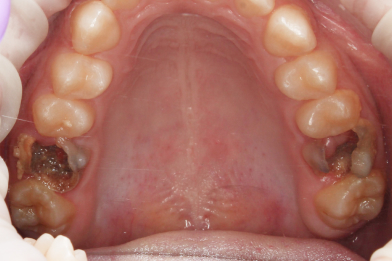

Жалобы на выпадение пломб. Произведено восстановление анатомо-физиологический формы

Бояринов Сергей Эдуардович

зубов при помощи пломбировочного материала. -